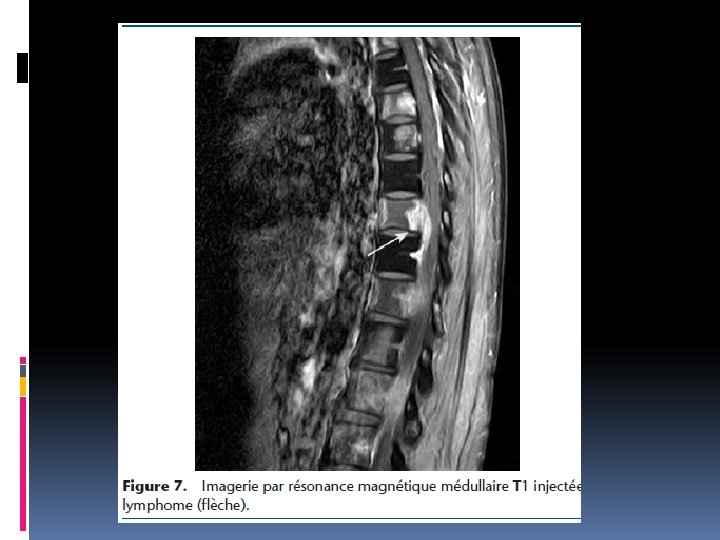

IV. Bilan paraclinique Tout tableau de compression médullaire franche et/ou d’aggravation rapide impose la réalisation d’une IRM panmédullaire en urgence Visualise les lésions épidurales, osseuses, le siège de la compression, son extension, lésions asymptomatiques à d’autres niveaux

VI. Etiologies a-Compression médullaire aigue: Trauma du rachis direct ou indirect ( AVP; chutes; …. ) b-compression médullaire chronique ou lente b-1: Causes extra-médullaires Causes rachidiennes: tumeurs vertébrales bénignes ou malignes (primitives ou secondaires) Causes intrarachidiennes: -extradurales: tumeurs épidurales malignes ; lipome -intradurales: neurinomes, méningiomes, autres tumeurs , processus non tumoraux dont abcès, parasitose , tuberculome b-1: Causes intra-médullaires Tumeurs: épendymome, gliome, angiome médullaire Infections: abcès, tuberculome, parasitose, syphilis